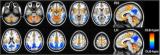

IEEE JBHI封面 | 胡战利研究员团队实现全脑区PET/MR高清成像

脑科学作为生命科学领域的重要前沿分支,其复杂性构成了科学研究中的一项重大难题。特别是如阿尔茨海默病、抑郁症、自闭症、帕金森病等神经退行性疾病和精神疾病领域,脑科学研究对于理解其神经生物学基础至关重要。结合解剖结构和功能代谢信息的一体化PET/MR设备,是目前神经系统疾病诊断和科学研究的一种重要多模态分子影像技术。然而,PET/MR扫描需要注射标准剂量的放射性示踪剂,增加了患者的辐射风险。近日,中国科学院深圳先进技术研究院... 2024-09-25 核技术核医学PET/MRI